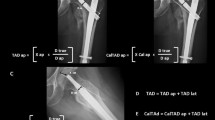

Dependent on the rotation of the C-Arm the antero-superior border, which is often hard to recognize, and postero-superior border of the GT overlap. This coincides with an overlapping of the density line of the piriform fossa and the intertrochanteric crest, which are both easily recognized in c-arm images. (Fig. 4) We named this line the cortical overlap line. The view in which the cortical overlap line is visible was defined as the Cortical Overlap View (COV) (Fig. 3). The position of the C-arm, in which the COV was achieved, was noted.

Defining the radiological landmarks. (a,b) and (c,d) are each pairs of an identical radiological view of the proximal femur. (c,d) both show the COV while (a,b) show an ap view, which deviates from the COV by 10° external rotation. (a) xray image with markers indicating the postero-superior border of the GT (*) and the anterio-superior border of the GT (**) as well as the tip of the GT (°). (b) the postero-superior border of the GT is the extension of the intertrochanteric crest (yellow). A density line of the piriform fossa is easily recognized (green). (c,d) the antero- and postero-superior borders of the GT overlap in the COV, this coincides with an overlapping of the easily recognizable intertrochanteric crest and density line of the piriform fossa.

Digital measurements were performed using ImageJ software (ImageJ v1.49, National Institutes of Health, USA). The distance between the cortical overlap line and the tip of the GT (Fig. 5), the distance between the posterior border of the GT to the tip of the GT in the various views and the antetorsion of the proximal femur (defined in the axial plane as the angle between the line defined by the posterior aspect of the distal femoral condyles and a line drawn from the centre of the femoral head to the midline of the femoral neck)15 were measured. The type of greater trochanteric overhang according to Grechenig et al. was evaluated in the axial radiograph16: group 1, with full access to the entry point; group 2, where the outline of the spine is projected laterally; group 3, where the entry point is partially covered and group 4, where the entry point is completely covered. The length of the femur was defined as the distance in millimetres from the tip of the GT to the most distal part of the lateral femoral condyle.